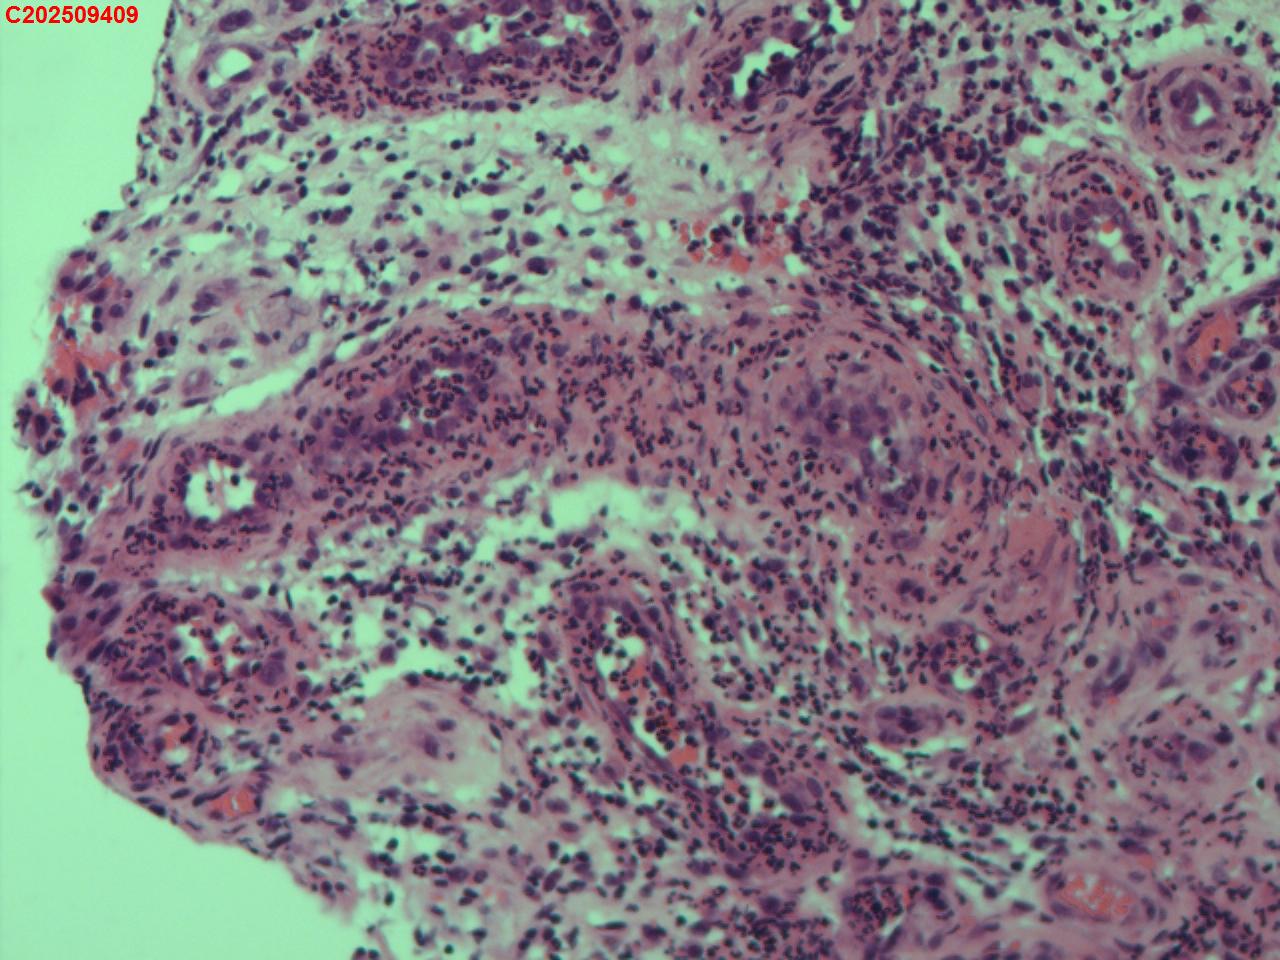

纤支镜咬检

性别年龄62岁临床诊断社区获得性肺炎,肺占位性病变带除外

一般病史胸部CT:双肺可见多发斑片状、结节状高密度影,右肺上叶及左肺下叶病灶内见多发空洞,右侧少量胸腔积液。

标本名称纤支镜咬检

大体所见纤支镜:气管通畅,隆突锐利。右肺主支气管通畅,右肺上叶见少量痰液,负压吸引后见上叶开口干酪坏死物质附着,上叶各段级支气管通畅未见新生物及坏死物质,中叶、下叶背段支气管通畅,下叶基底段见新生物阻塞气道,粘膜无充血。左肺主支气管、上叶、下叶及各段级支气管通畅,粘膜无充血,未见新生物及坏死物。

考虑:支气管炎性息肉